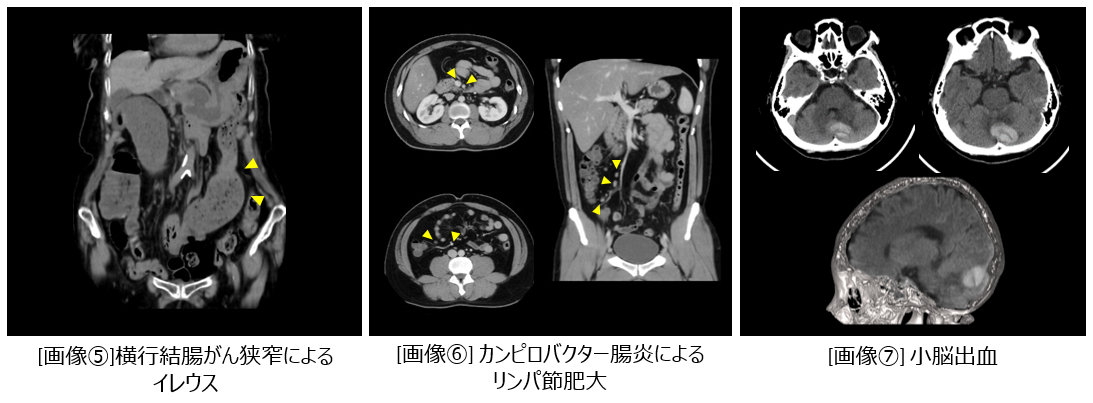

大腸がん(リンパ節転移を伴う) [画像③]、胆嚢がん [画像④]、横行結腸がん狭窄によるイレウス[画像⑤]、カンピロバクター腸炎によるリンパ節肥大 [画像⑥]などの消化器領域病変を検査できています。消化器領域以外では目眩を訴える患者様の頭部を撮影したところ小脳部分に出血を認めました。 [画像⑦]

actcv_sakamoto_naika_060708_big.png